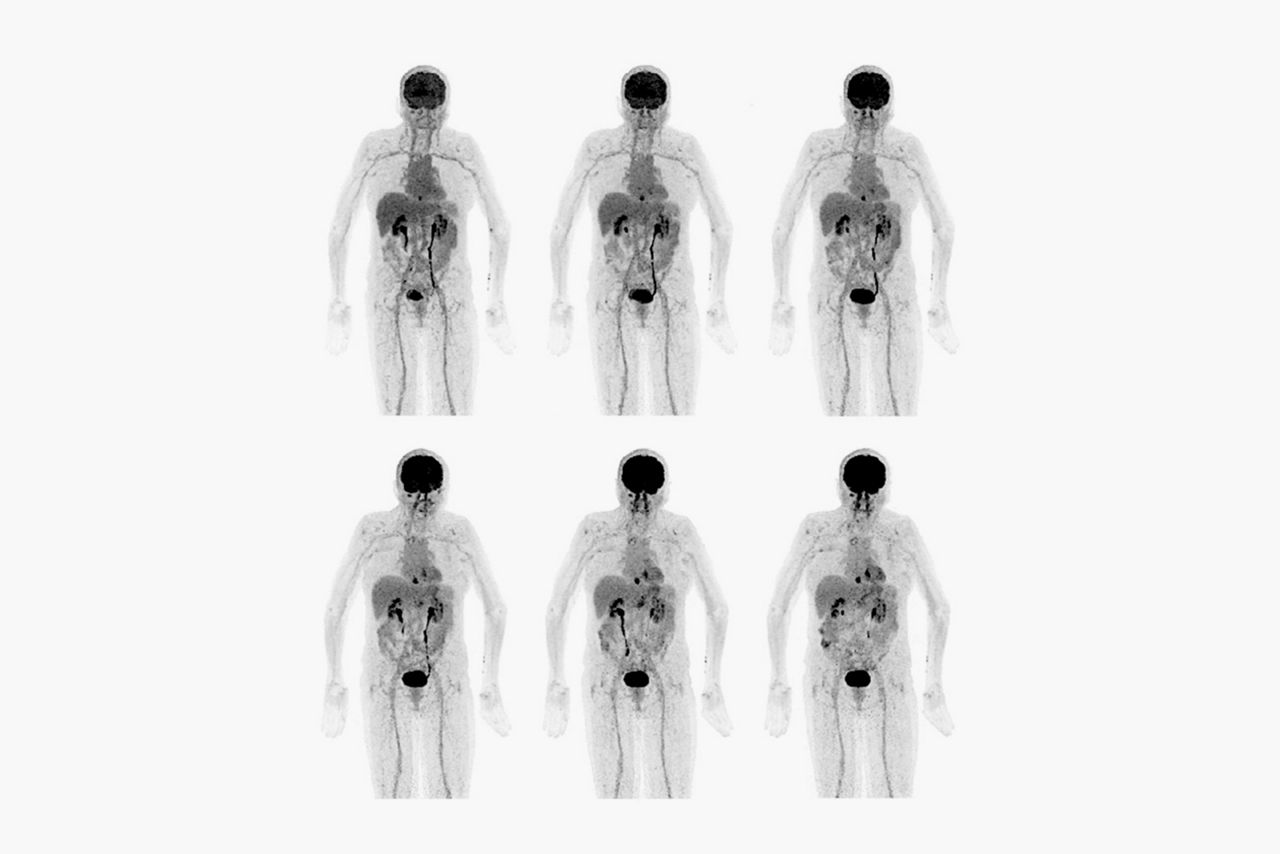

In PET imaging, sensitivity is everything. It affects your ability to detect small lesions, your scan length and dose amounts. Each row of the Discovery MI Gen 2 LightBurst Digital Detector adds five centimeters to your total field of view. Discovery MI Gen 2 can expand all the way up to 30 centimeters of coverage, providing a 50 percent increase in peak NECR3, as well as exceptional system sensitivity that reaches 30 cps/kBq.

Static whole-body PET/CT imaging provides a simple snapshot of radiopharmaceutical concentration, but it takes time to truly understand how tissue is behaving. With whole-body dynamic imaging, you can see the difference between tracer activity that’s simply trapped in tissue versus highlighting actual malignancies. Capturing this level of information takes time. Discovery MI Gen 2 delivers the FOV and the sensitivity necessary to enhance whole-body dynamic acquisition. It allows you to capture as much detail as possible in fewer bed positions. With Discovery MI Gen 2 and WB Dynamic IQ Protocol4, you have a powerful new tool that provides you with the ability to better identify regions of metabolic activity and increased tracer uptake rate5.